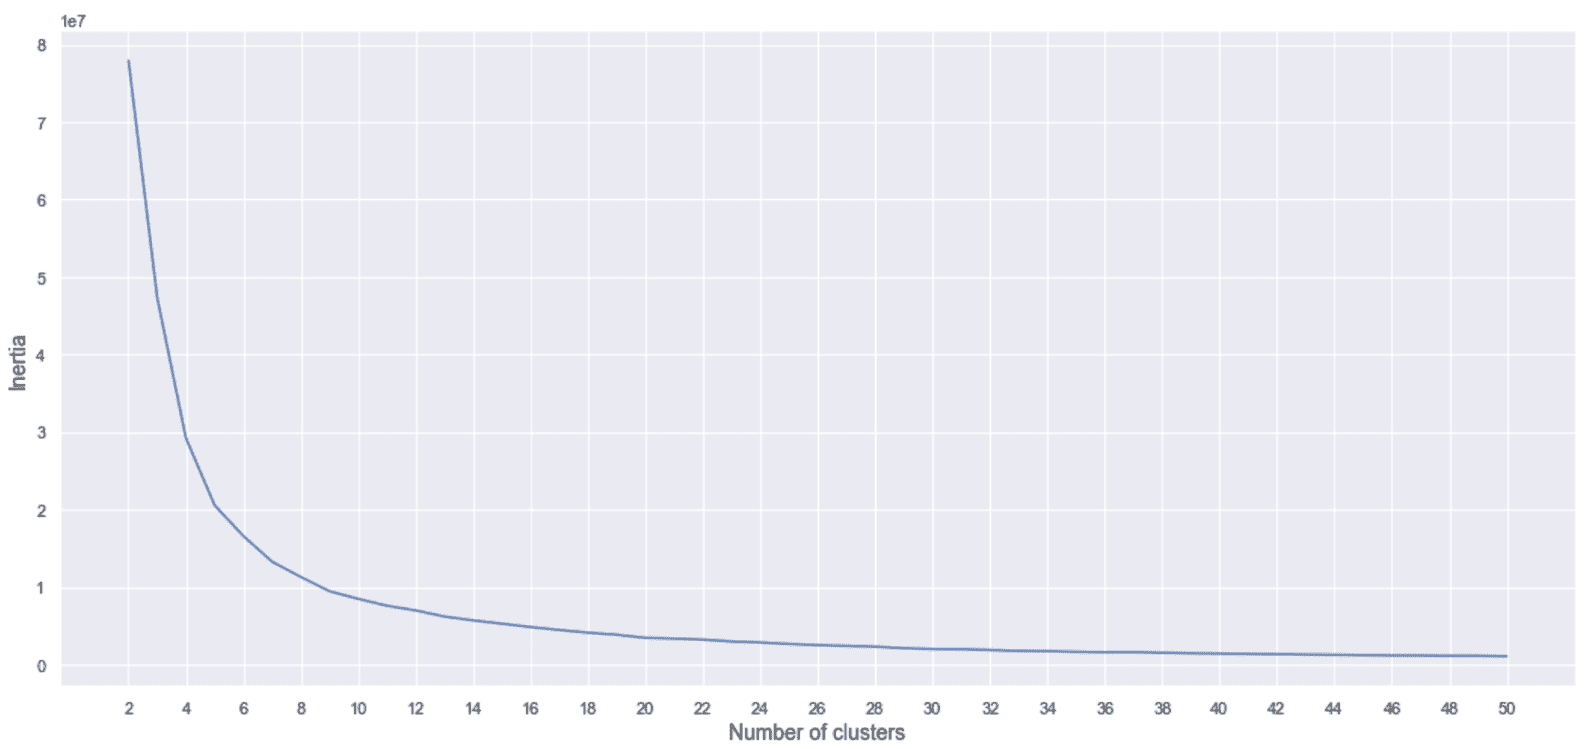

现在,我们可以使用K ∈ [2, 50],的乳腺癌威斯康星数据集重复该实验,如下所示:

from sklearn.cluster import KMeans

inertias = []

for i in range(2, 51):

km = KMeans(n_clusters=i, max_iter=1000, random_state=1000)

km.fit(cdf)

inertias.append(km.inertia_)

生成的绘图显示在以下屏幕截图中:

惯性,作为乳腺癌威斯康星州数据集的群集数的函数

在这种情况下,基本事实表明,我们应该根据诊断将其分为两组。 但是,该图显示了急剧下降,下降到K = 8并以较低的斜率继续,直到大约K = 40为止。 在初步分析过程中,我们已经看到二维投影由具有相同诊断的许多孤立的斑点组成。 因此,我们可以决定采用例如K = 8并分析与每个群集相对应的特征。 由于这不是分类任务,因此可以将真实情况用作主要参考,但是正确的探索性分析可以尝试理解子结构的组成,以便为技术人员(例如,医生)提供更多详细信息。